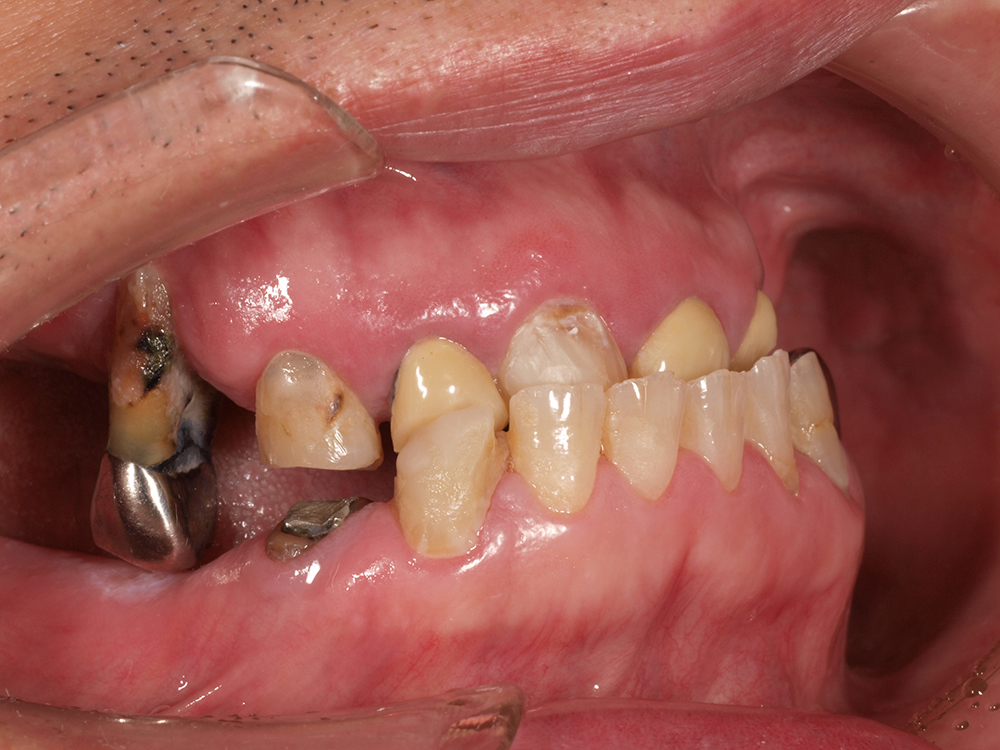

55歳 男性

- 主訴

- 前歯でしか咬めなく、食事を採るのに非常に困難で辛い

- 処置内容

- 上顎6本、下顎3本

- 治療費用

- 上顎:約230万(税込)下顎:約120万(税込)

- 治療期間

- 上顎:1年(仮歯まで8か月)下顎:8か月(仮歯まで5か月)

- リスク

- 上部構造物、仮歯の破折、術後の腫れ(3日)、人工歯根脱落リスクがあります